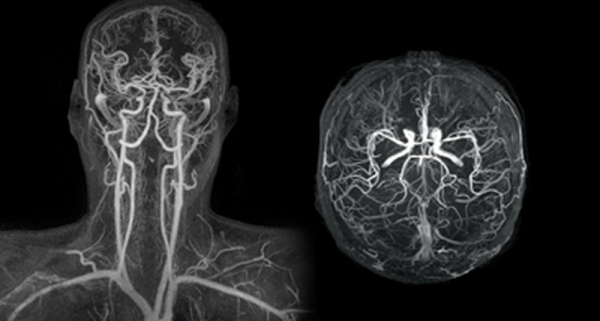

Μαγνητική Αγγειογραφία (MRA)

Η Μαγνητική Αγγειογραφία (MRA) είναι μια μη επεμβατική εξέταση που χρησιμοποιεί τη μαγνητική τεχνολογία και τους υπολογιστές για να δημιουργήσει λεπτομερείς εικόνες των αγγείων στο εσωτερικό του σώματος, συμπεριλαμβανομένων των αρτηριών και των φλεβών. Η MRA χρησιμοποιεί το μαγνητικό πεδίο και ραδιοκύματα για τη δημιουργία λεπτομερών εικόνων των αγγείων, χωρίς τη χρήση ακτινοβολίας.

Υπάρχουν διάφοροι τύποι MRA, και ορισμένοι από τους συνηθέστερα χρησιμοποιούμενους περιλαμβάνουν:

-

Time-of-Flight MRA (TOF-MRA): Αυτή η μέθοδος εκμεταλλεύεται τη διαφορά στη ροή του αίματος για να δημιουργήσει εικόνες των αγγείων. Είναι ευαίσθητη στη ροή του αίματος και συνήθως χρησιμοποιείται για την αξιολόγηση των αρτηριών.

Contrast-Enhanced MRA (CE-MRA): Σε αυτήν τη μέθοδο, ενέσεις με χρωστικές ουσίες που είναι ορατές στις εικόνες μαγνητικής αγγειογραφίας εισέρχονται στην κυκλοφορία του αίματος για να προσδώσουν αντίθεση στις εικόνες. Αυτή η μέθοδος παρέχει πιο λεπτομερείς εικόνες των αγγείων και είναι ευαίσθητη στη ροή του αίματος.

Η MRA χρησιμοποιείται συχνά για την αξιολόγηση των αγγείων σε διάφορα μέρη του σώματος, συμπεριλαμβανομένων των καρωτίδων, της κοιλιακής αορτής, των εγκεφαλικών αγγείων και άλλων περιοχών. Είναι χρήσιμη για την ανίχνευση στενώσεων, ανευρυσμάτων, ή άλλων ανωμαλιών στο σύστημα κυκλοφορίας του αίματος.